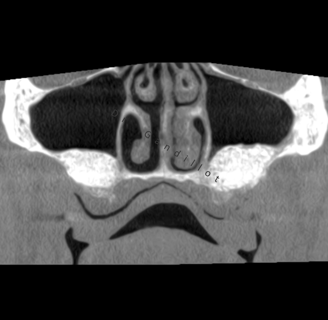

Les sinus sont des cavités dans l’os du massif facial, au-dessus des prémolaires et des molaires.

Après extraction des prémolaires et molaires maxillaires, la hauteur osseuse disponible sous le sinus maxillaire n’est souvent pas suffisante pour insérer un implant dentaire.

Il est nécessaire de surélever le plancher sinusien, cette procédure est également appelée sinus lift ou greffe osseuse sous-sinusienne.